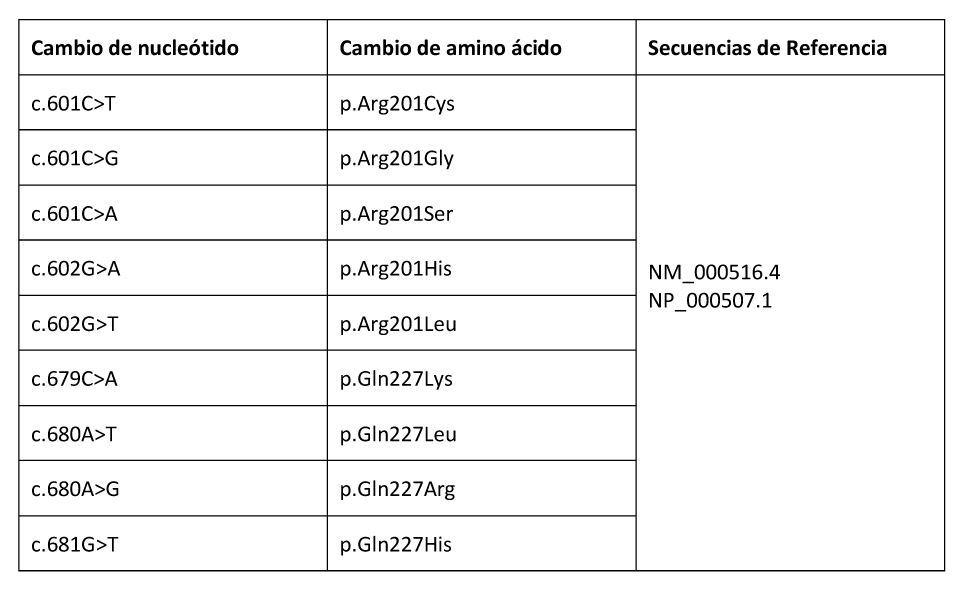

A día de hoy, sólo se han identificado mutaciones en los codones p.Arg201 y p.Gln227 de GNAS. La gravedad de la enfermedad se correlaciona con el grado de mosaicismo y los tejidos afectos.

El diagnóstico de DF/MAS puede establecerse en individuos que presenten 2 o más hallazgos clínicos típicos. Para confirmar el diagnóstico en aquellos individuos en los que el único hallazgo clínico sea la DF monostótica, se requerirá la identificación de las variantes patogénicas en el gen GNAS (codones p.Arg201 (>95% de los casos, siendo especialmente frecuente la sustitución por cistina e histidina (p.Arg201Cys y p.Arg201His)) y p.Gln227 (<5% de los casos siendo especialmente frecuente la sustitución por Leucina (p.Gln22Leu)).

Variantes patogénicas: Se ha identificado la mutación somática con cambio de sentido (missense mutation) p.Arg201 en más del 95% de los casos publicados de DF/MAS. Las variantes patogénicas más frecuentes son p.Arg201His y p.Arg201Cys (Lumbroso et al 2004). Más raramente, la arginina es sustituida por serina, glicina o leucina. También se ha reportado, aunque de manera excepcional, la variante patogénica p.Gln227 (Idowu et al 2007).

Tabla 8. Variantes de GNAS Somáticas Comentadas en esta Revisión